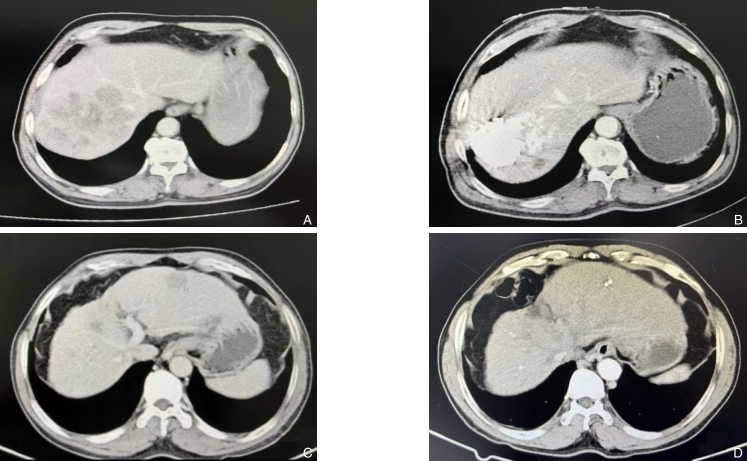

Abstract:Background and Aims For borderline resectable primary liver cancer, the recommended treatment options currently in China according to the Diagnosis and Treatment Guidelines for Primary Liver Cancer (2022 edition) are still transcatheter arterial chemoembolization (TACE), surgical resection, or systemic anti-tumor therapy. Preoperative conversion therapy for primary liver cancer has made significant progress, but specific conversion therapy strategies are still under exploration. This study was performed to explore the real-world efficacy of local conversion therapy using FOLFOX regimen-based hepatic arterial infusion chemotherapy (HAIC) plus transarterial embolization (TAE) in the treatment of borderline resectable liver cancer.Methods The clinical data of 22 patients with borderline resectable (CNLC stage IIb) primary liver cancer who underwent conversion therapy using FOLFOX regimen-based HAIC combined with TAE from April 2019 to February 2022 were collected. Tumor objective response rate (ORR) and disease control rate (DCR) were assessed based on the modified response evaluation criteria in solid tumors (mRECIST). The conversion surgery rate, pathological response rate in postoperative specimens, and the prognosis of patients undergoing or not undergoing surgery after conversion therapy were analyzed.Results All 22 patients completed HAIC combined with TAE treatment. Main adverse reactions included upper abdominal pain, low-grade fever, and short-term liver dysfunction, but no irreversible severe complications occurred. After conversion therapy, the tumor ORR and DCR were 63.6% and 86.3%, respectively, and 3 patients (13.6%) experienced tumor progression. Following the completion of conversion therapy, 14 patients underwent liver cancer resection, and the conversion surgery rate was 63.6%. All surgeries were successfully performed and all achieved R0 resection. There were no postoperative deaths. Postoperative pathology showed major pathological response (MPR) in 10 cases (71.4%), but none achieved complete pathological response (CPR). The average disease-free survival for surgical patients was 14.7 months, and their overall survival was significantly better than non-surgical patients (22.7 months vs. 13.2 months, P=0.018).Conclusion HAIC plus TAE conversion therapy for borderline resectable liver cancer demonstrates excellent tolerability, proving to be a safe and feasible approach that achieves higher ORR, DCR, and conversion surgery rate. Although most patients achieve MPR after preoperative conversion therapy, CPR remains low. So, surgical resection still the key approach for patients to attain long-term survival after liver cancer conversion therapy.